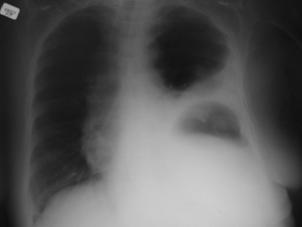

Hemotorace stang masiv Hemotorace stang masiv

Hemotorace

drept masiv Hemotorace stang

Imagine CT Radiografie efectuata in ortostatism

Hemotorace drept Hemo-pneumotorace stang

Radiografie efectuata in clinostatism